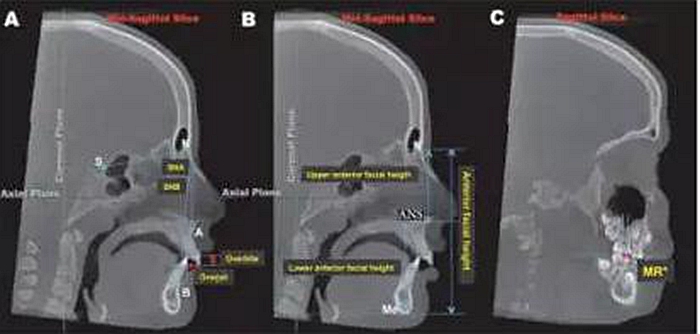

圖1:3D參考平面的的定為:軸面:通過(guò)左右眶下點(diǎn)及右側(cè)耳點(diǎn)的平面;冠狀面,通過(guò)左右耳點(diǎn)并垂直于軸面的平面;矢狀面,通過(guò)鼻根點(diǎn)并垂直于軸面及冠狀面的平面。

圖2:矢狀面上標(biāo)志點(diǎn)的測(cè)量:A,SNA, SNB, 覆合覆蓋的測(cè)量;B,上前面高N-ANS,下前面高ANS-Me的測(cè)量;C,左右磨牙關(guān)系的測(cè)量:上頜第一磨牙近中頰尖與下頜第一磨牙近中頰溝的水平距離,但在擴(kuò)弓完成的即刻(T2)因?yàn)槟パ缼Лh(huán)的阻擋,該數(shù)據(jù)無(wú)法測(cè)量。